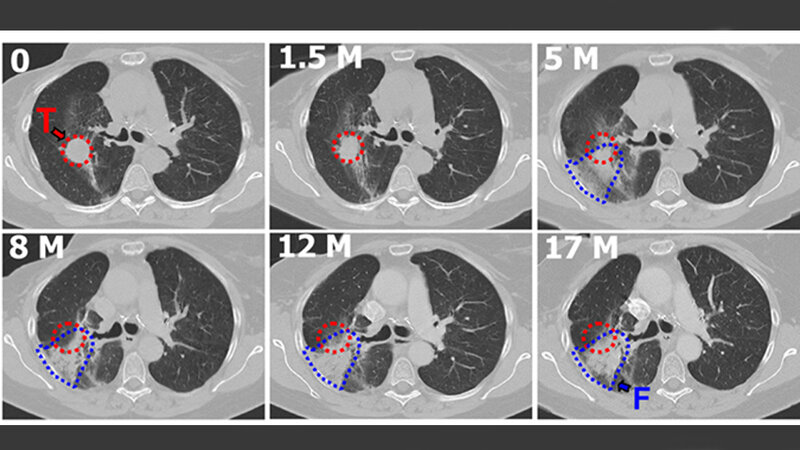

Huber und Kollegen erprobten nun an Mäusen einen Antikörper, der den Bindegewebe-Wachstumsfaktor (CTGF, connectiv tissue growth factor) blockiert. CTGF gilt als zentraler Signalgeber bei der bindegewebigen Umwandlung des Lungengewebes. Die Forscher verabreichten Mäusen den Antikörper über acht Wochen, beginnend zu verschiedenen Zeitpunkten vor oder nach einer Bestrahlung.

Alle Therapieschemata schützen bis zu 80 Prozent der Tiere vor einer Fibrose. Bei einem Start der Behandlung 16 Wochen nach der Bestrahlung machte der Antikörper eine fibrotische Umwandlung wieder rückgängig: Die Dichte des Lungengewebes verringerte sich um über 50 Prozent, die Lungenfunktion und die Sauerstoffversorgung verbesserten sich. Auch nach Abschluss der Behandlung blieb der Gesundheitszustand der Tiere stabil und sie überlebten deutlich länger als unbehandelte Mäuse.